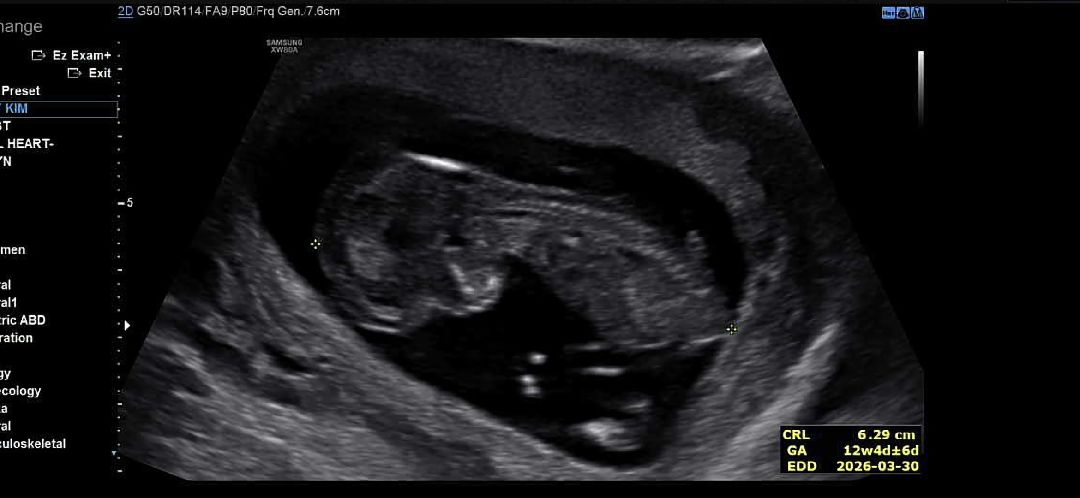

오늘 1차 기형아 검사하고 왔는데 처음 딱 봤을때 선생님이 계속 이리저리 굴려주시길래 각도마다 보여주시는구나 했는데 그게아닌 아가 목투명대가 잘 보이지않는데 두께도 두꺼운거 같다고 조금 있다가 다시 해보자하셔서 30분 뒤에 다시하고 또 안 좋아서 3번이나 했습니다... 그나마 보인 사이즈는 약 5mm?... 두꺼운거같다고 니프티 검사를 권하시더라구요.. 원래 4쥐 뒤 2차 기형아 검사를 해야되는데 2주듀ㅣ에 다시 봐주시겠다고 그때 다시 오래요 괜찮을까요...? 너무 마음이 안 좋네요...